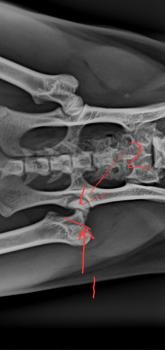

Leider keine guten Nachrichten von unserem Pechvogel Takumi. Er muss in seiner Gruppe beim Sprung vom Kratzbaum - oder was auch immer – schlecht aufgekommen sein. Jedenfalls war der Kopf des Femurs, des Oberschenkelknochens, sehr unglücklich gebrochen. Eine für uns sehr kostspielige Diagnose. Denn Takumi musste operiert werden. Die Kostenvoranschläge, die wir eingeholt haben, beliefen sich auf teilweise mehr als 600 Euro für die OP. Schließlich hat es unserer Tierarzt für ungefähr die Hälfte gemacht. Immer noch sehr viel Geld – aber wir mussten dem kleinen Mann doch helfen.. Jetzt hoffen wir sehr, dass Takumi im wahrsten Sinne des Wortes wieder auf die Beine kommt. Takumi sitzt im Moment im Käfig und wird dort sicher auch noch eine geraume Zeit bleiben müssen. Ob er wieder ganz normal laufen kann, oder ein leichtes Hinken zurückbleibt, vermögen wir im Moment noch nicht zu sagen. Das Maul wurde bei dieser Gelegenheit übrigens auch nochmal kontrolliert. Das sieht inzwischen gut aus. Nur die leichte Verziehung seiner Lippe, die ist geblieben. Und ein „Hauer“ fehlt dem kleinen Mann. In solchen Momenten wird uns wieder schmerzhaft bewusst, dass wir immer weniger Paten für unsere Katzen haben - so wie für Takumi. Jetzt sitzen wir auf der hohen OP-Rechnung (Spenden sind herzlichst willkommen!), und mussten und müssen seit inzwischen einem Jahr zudem noch den Unterhalt von Takumi stemmen. Ohne Paten, so viel steht fest, können wir auf Dauer unsere Arbeit vor Ort gar nicht leisten. Takumi lässt sich im Käfig übrigens inzwischen anfassen. Er genießt das noch nicht richtig, aber es wird- peu a peu. Will denn wirklich niemand unserem hübschen Pechvogel Takumi ein Zuhause schenken?